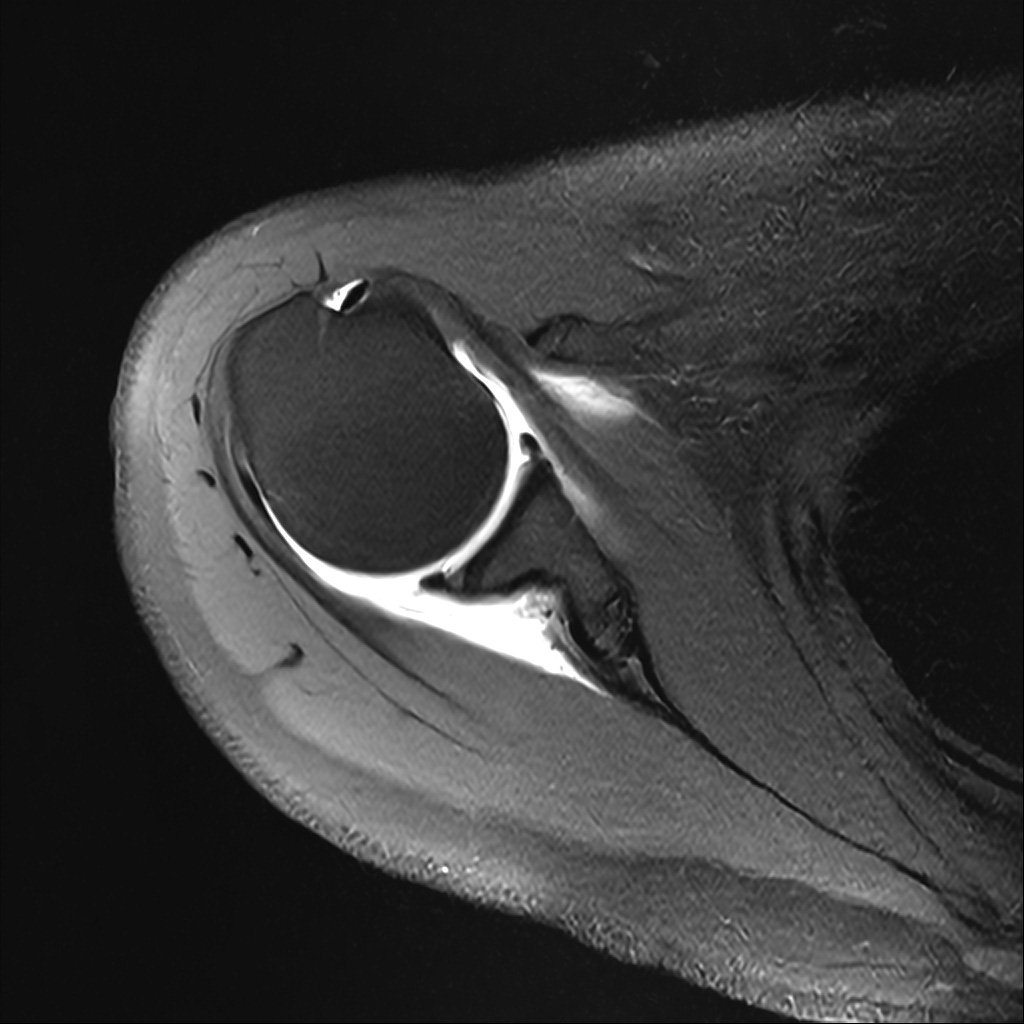

Mri 단면 영상으로 보아 어깨 관절 부위에서 이상 신호가 관찰되고 이는 관절 와순 파열의 가능성을 시사할 수 있습니다.

하지만 이영상만으로 정확한 진단은 불가능하고 정밀한 판단을 위해선 전체 시퀀스와 영상의학과 전문의의 공식판독이 필요합니다 특히 와순 파열은 위치와 동반 병변에 따라 해석이 달라집니다!